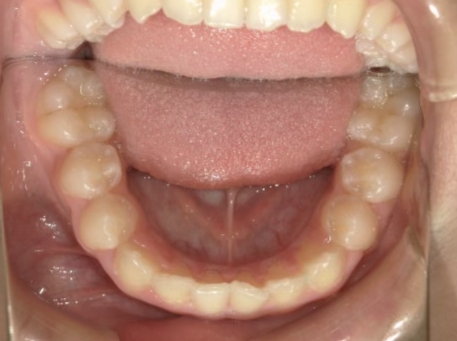

治療中⑤ 小5:10y11m

モノブロック装置継続中、左上3が八重歯で萌出